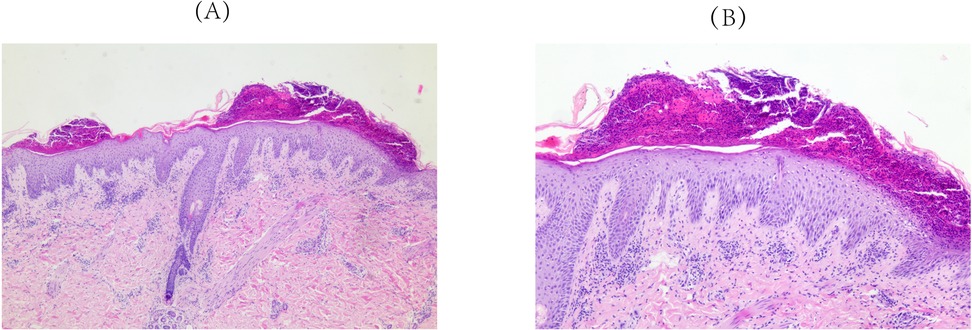

Approximately 3 weeks after HCQ therapy, the patient developed a progressively worsening pruritic pustules, which progressed from the lumbar area to the facial, truncal, and extremity regions (Figure 1). A skin biopsy of the right upper limb pustular eruptions showed epidermal hyperkeratosis with parakeratosis, pustule formation above the stratum spinosum and acanthosis. Neutrophils and lymphocytes were observed in the superficial and mid-dermal vascular plexuses (Figure 2).

Figure 2. Pathological findings of skin biopsy (right upper limb). Epidermal hyperkeratosis with parakeratosis, pustule formation above the stratum spinosum and acanthosis. Neutrophils and lymphocytes localizes to the superficial and mid-dermal vascular plexuses were observed. (A) Original magnification ×50, (B) Original magnification ×100; hematoxylineosin staining.